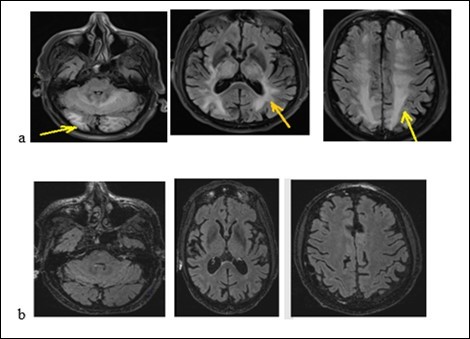

An old man of 74 called J. R. was admitted to hospital on January 26, 2018 for generalized tonic-clonic seizures. The symptoms began 2 weeks before his admission by abdominal pain, vomiting, diarrhea without fever. They were followed by generalized tonic-clonic seizures. According to his medical history, he suffers from high blood pressure, non-insulin-dependent diabetes, chronic obstructive pulmonary disease (COPD), moderate renal failure on a single kidney. He underwent a left nephrectomy for a papillary urothelial tumor, a right upper pulmonary lobectomy for the removal of a bronchial adenocarcinoma. He has been treated with Gemcitabine (Gemzar) and by Fluorine uracil (Folfox) for a pancreatic adenocarcinoma. He also has 3 adrenal nodules. The physical examination noted drowsiness but the patient was reactive to minor stimuli with a Glasgow score of 13/15, a flaccid right hemiplegia. We noted that there was not a neck thifness. Besides, the blood pressure was 210/95 mm Hg and the heart rhythm was regular without heart murmur or additional noises. The rest of the physical examination was normal. The biological check-up had shown a creatinine level at 203 micromol/l with a clearance at 29.9 ml/min, a hyperkalaemia at 6 mmol/l and a hypercalcemia at 2.62 mmol/l. The CSF study had shown a hyperproteinorachy at 0.940g / l, a glycorachy at 5.6 g/l, the CSF count cell displayed 6 cells/mm3 without germ. The brain MRI (Figure 4a) had displayed on flair sequences, diffuse and symmetrical hyper signals of the sub-cortical white matter of the temporal, occipital, frontal lobe and the cerebellum. These radiological findings evoked a RPE syndrome. The treatment included hyperhydration and an anti-epileptic drug. The outcome was noticeable with the decrease of symptoms. We relied on the diagnosis of RPE syndrome. The brain MRI checking-up (Figure 4b) at 40 days was displaying a complete decrease of the lesions.

Figure 4.Brain MRI with flair sequences showing hyper signals of white matter and cerebellum corresponding to edema (a) and the decrease of lesions after treatment (b).

Brain MRI with flair sequences showing hyper signals of white              matter and cerebellum corresponding to edema (a) and the decrease of              lesions after treatment (b).